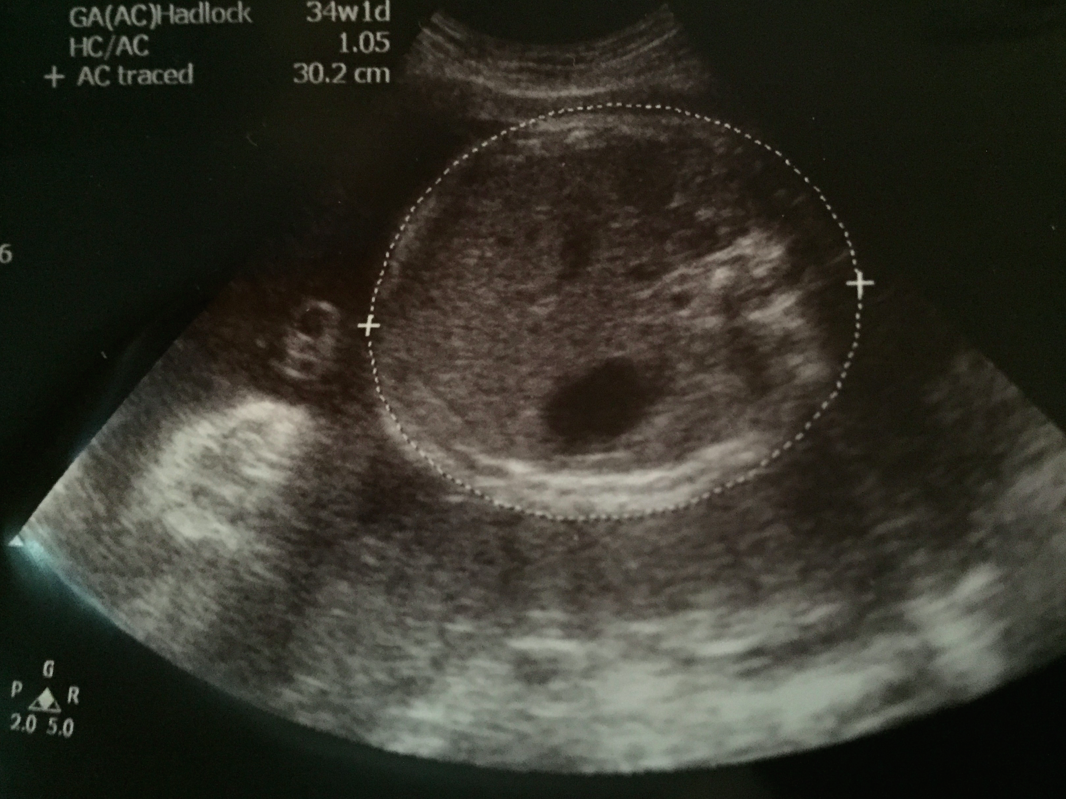

頭仔﹗超聲波相上面顯示嘅週數係頭圍,S醫生話直徑其實比起頭圍有代表性,直徑係完美嘅33週的﹗

個graph plot出嚟同之前都好consistent丫﹗頭仔一直都along 50 percentile,肚圍同腿長都比較大少少,relatively好似真係好長腿喎~今日用算式計出嚟嘅估計體重係2.26kg﹗都有啲手感啦~